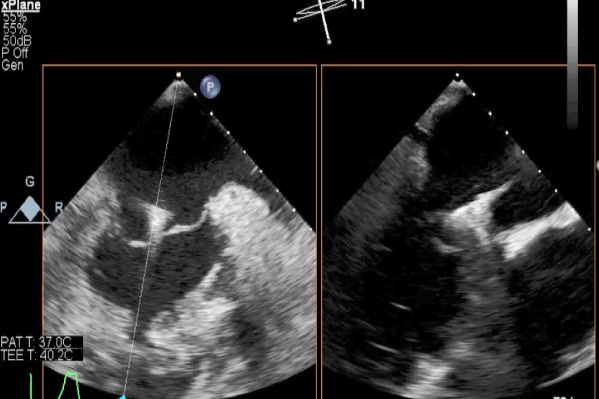

TEE短轴脱垂区域显示(P2、P3区大范围脱垂)

TEE短轴脱垂区域显示(color,血流来源于P2、P3区)

三维超声心动图显示第一枚XTR夹子释放,残余返流主要位于外侧

三维超声心动图显示第二枚XTR夹子释放